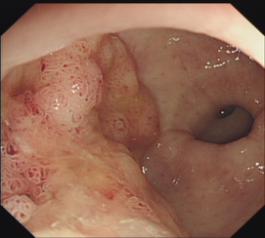

结肠腺瘤粘膜剥离术